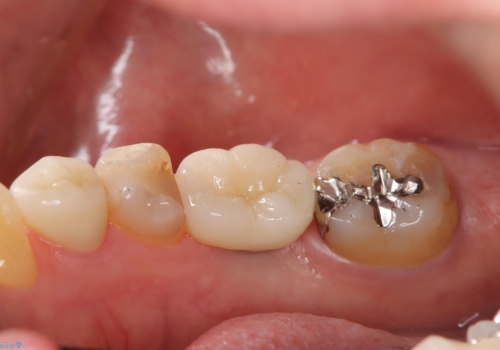

- 定期的に本院に通院されている患者様で、前歯の揺れがあると相談されました。下の奥歯が左右合わせて3本喪失されており、噛み合わせの負担が前歯にも集中していることを説明しました。右下6番の歯に関しては、事前の診査で十分な骨量がありましたのでインプラントを1本埋入しました。左下5番・6番にも本来はインプラントを埋入したかったのですが、骨量が十分でなく、骨を増やす処置をすると神経が近くリスクがあることから、審美性に配慮した金属のばねが見えないノンクラスプデンチャーを製作しました。また、このとき入れ歯を支える左下7番に根尖病変がありましたので、根管治療も行っております。(根管治療は当院院長で専門医を持つDr.林が担当しています。)治療終了後、約1年が経過しましたが、問題なく経過しており患者様も喜ばれていました。